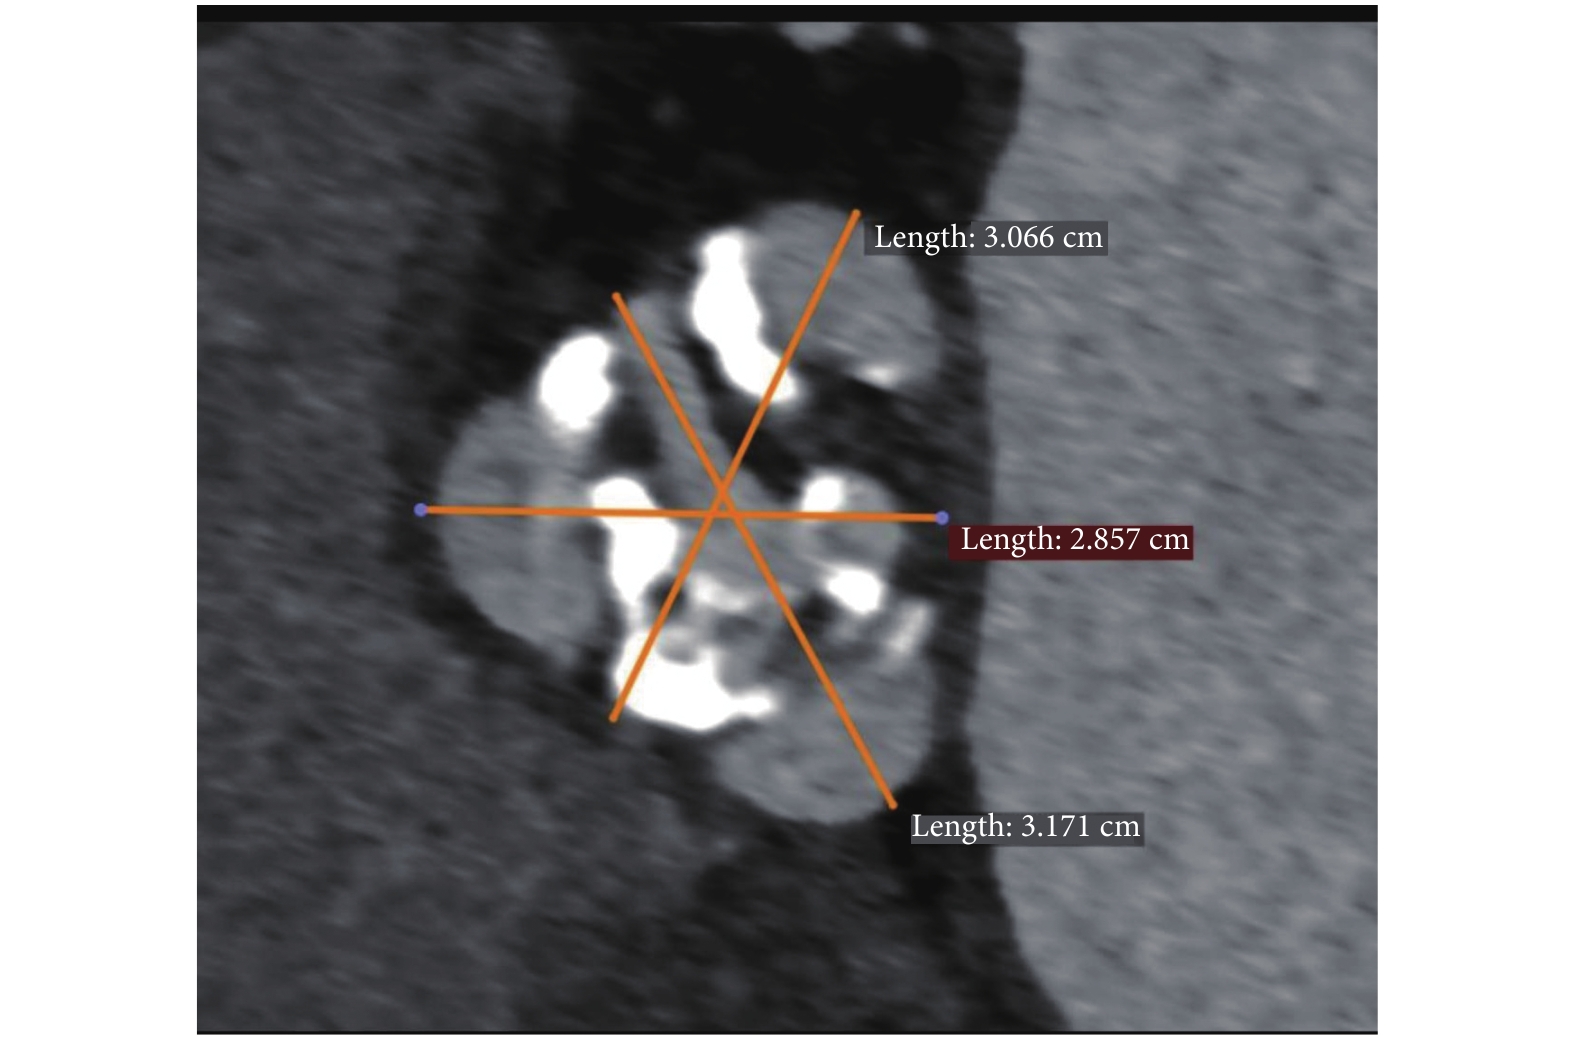

病例 2:男,72 歲,因“活動后胸悶、氣促 1 年余”收入我科。體格檢查:血壓 154/46 mm Hg,雙下肺少許濕羅音;心率 88 次/分,主動脈瓣區舒張期雜音。超聲心動圖:主動脈瓣中-重度關閉不全,三葉瓣,左心房內徑(LAD) 41 mm,左心室舒張期末內徑(LVEDD) 55 mm,主動脈瓣口反流峰速 4.26 m/s;升主動脈擴張直徑 38 mm;LVEF 0.62;二尖瓣、三尖瓣輕度反流。三維增強 CT:升主動脈擴張,最粗直徑約 36 mm;三葉主動脈瓣,無明顯鈣化,測量瓣環徑 26.64 mm(圖 4);冠狀動脈開口高度分別是 15.8 mm 和 17.6 mm;胸腹主動脈壁多發散在鈣化、局部穿透性潰瘍、局限性壁間血腫形成;6 分鐘步行試驗 280 m;STS 評分 4%。術前診斷:(1)心臟瓣膜病、主動脈瓣中-重度關閉不全、升主動脈擴張、二尖瓣輕度反流、三尖瓣輕度反流、心臟擴大、心功能分級 (NYHA)Ⅲ 級;(2)高血壓三級、極高危組;(3)COPD;(4)胸、腹主動脈多發穿透性潰瘍并壁間血腫;(5)多發陳舊性腔隙性腦梗塞;(6)動脈粥樣硬化。手術中麻醉準備、穿刺建立軌道、切口暴露方法均同病例 1。經心尖安置 27 mm J-Valve@ 介入瓣膜,釋放定位鍵時發現無冠竇的定位鍵隨心跳擺動很厲害,定位鍵沒有進入竇內(圖 5),經反復調整確保三個定位鍵準確進入了瓣竇內,穩住位置緩慢釋放,防止瓣膜上跳、脫落、移位。造影及 TEE 確認瓣膜位置良好,無瓣周漏(圖 6)。患者循環穩定,舒張壓升高。退器械后心尖荷包打結止血,拮抗肝素,放置左胸腔引流管,關胸。術后 4 h 拔除氣管插管;術后 6 h 進食并下床活動;華法林抗凝至術后 3 個月,留臨時起搏電極 7 d;術后康復順利出院,心功能分級(NYHA)Ⅰ級;6 分鐘步行試驗 500 m。無瓣周漏、傳導阻滯等任何相關并發癥發生。隨訪9 個月無不適,復查超聲心動圖結果見表 2。